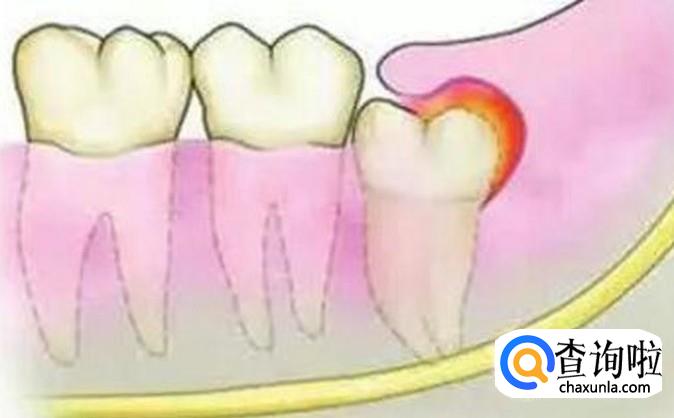

其次,如果我们的智齿总是导致我们的嘴巴处发炎的话,那么这样的智齿往往是需要拔除的,因为总是发炎对身体的伤害也是比较大的,这时候是必须要拔的,拔除后,我们需要确保不感染才行。